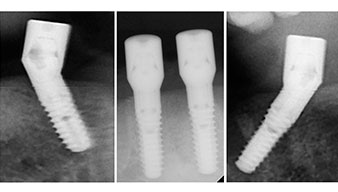

Este valor se corresponde con la posición siguiente del ajuste predefinido en Implantmed. Aquí se aprecia la inclinación de aproximadamente 45 grados del contra-ángulo de W&H hacia medio caudal en la región de la pieza 45 para preservar el nervus mentalis. El foramen mentale sirve como orientación anatómica para todas las perforaciones en esta zona. Las perforaciones siguientes se realizaron con una velocidad reducida de 300/rpm (figs. 10 y 11).

El siguiente ajuste programado es la propia inserción de los implantes. En nuestra clínica, solemos insertar los implantes con una fuerza de 32 Ncm de manera estándar (figs. 12 y 13).

El requisito imprescindible para el tratamiento inmediato es una alta estabilidad primaria. Para satisfacer dicho requisito, en este caso, se prescindió del corte de rosca. La unidad de accionamiento Implantmed de W&H empleada aquí, posee un modo propio para ello que también puede seleccionarse directamente y resulta imprescindible para muchas indicaciones. Los últimos giros para la inserción del implante superaron el valor de 32 Ncm, por lo que se realizaron manualmente. En tales casos, se recomienda utilizar la función autocortante de los implantes y girar el implante varias veces hacia delante y hacia atrás de forma que el implante se aproxime gradualmente hasta su posición definitiva sin ejercer una presión excesiva sobre el hueso (fig. 14).